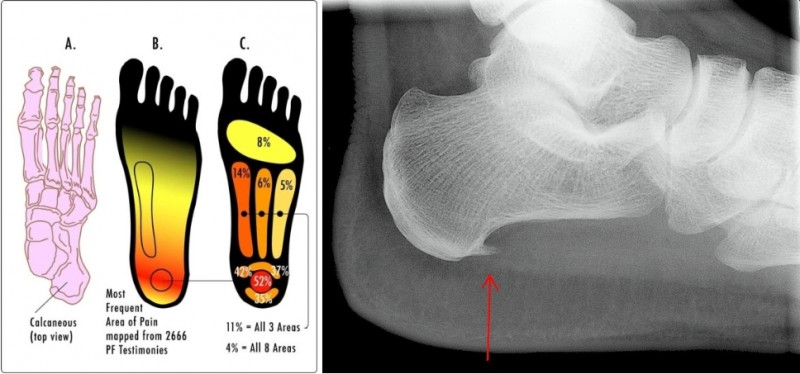

족저근막염은 발뒤꿈치뼈에서 시작해 발바닥 앞쪽으로 이어지는 강인한 섬유띠인 족저근막에 반복적인 미세 손상이 가해져 발생하는 염증성 질환입니다.

드물지만 발 뒤꿈치 뼈 부착부위에 뼈조각이 튀어나온 사람들 중 일부에서 발생하기도 합니다.

발뒤꿈치 안쪽에 집중되는 통증

발바닥 전체로 퍼지는 통증

특정 부위를 눌렀을 때 통증 발생